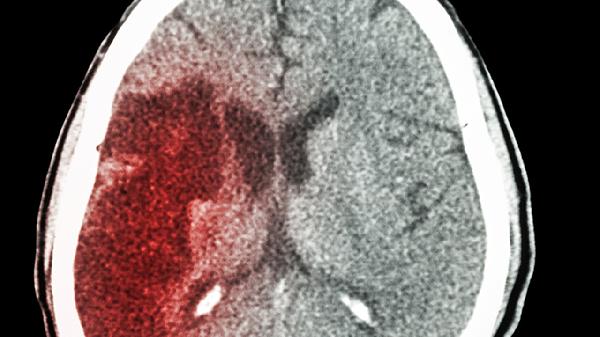

66岁老人突发脑梗,医生追问生活细节:他说出了一个“隐秘习惯”

66岁的老张怎么也没想到,一个看似无害的小习惯,差点要了他的命。那天早晨,他像往常一样准备起床,突然发现半边身体不听使唤,说话也变得含糊不清。送到医院后,医生诊断是急性脑梗,而在详细询问生活习惯时,老张透露了一个让医生直摇头的"隐秘习惯"。